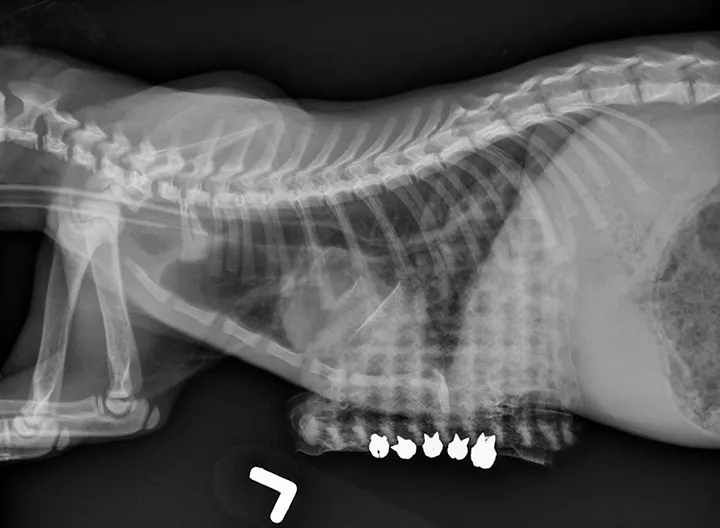

A lateral thoracic radiograph of a cat with a radiopaque mesh-like structure overlying the caudoventral aspect.

FIGURE 2

Patient in Figure 1. The sternum has been pulled ventrally and secured by circumsternal sutures to an external brace with removable split shot fishing sinkers.